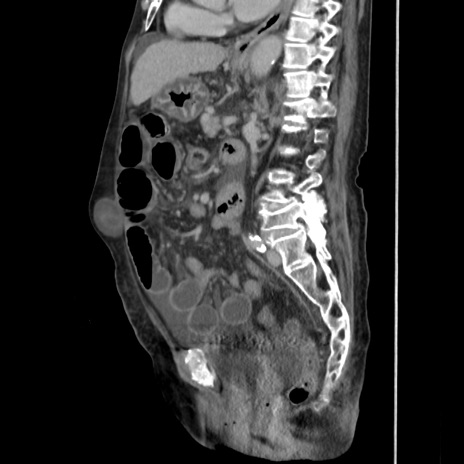

症例31(矢状断像)

【症例】80歳代 女性

【主訴】腹部膨満感

【現病歴】他院にて肝硬変にてフォロー中。1週間前から便秘、腹部膨満感、臍部腫瘤あり受診となる。

【既往歴】肝硬変

【身体所見】腹部膨隆あり、皮膚変化なし、疼痛なし。

【データ】WBC 4600、CRP 0.25